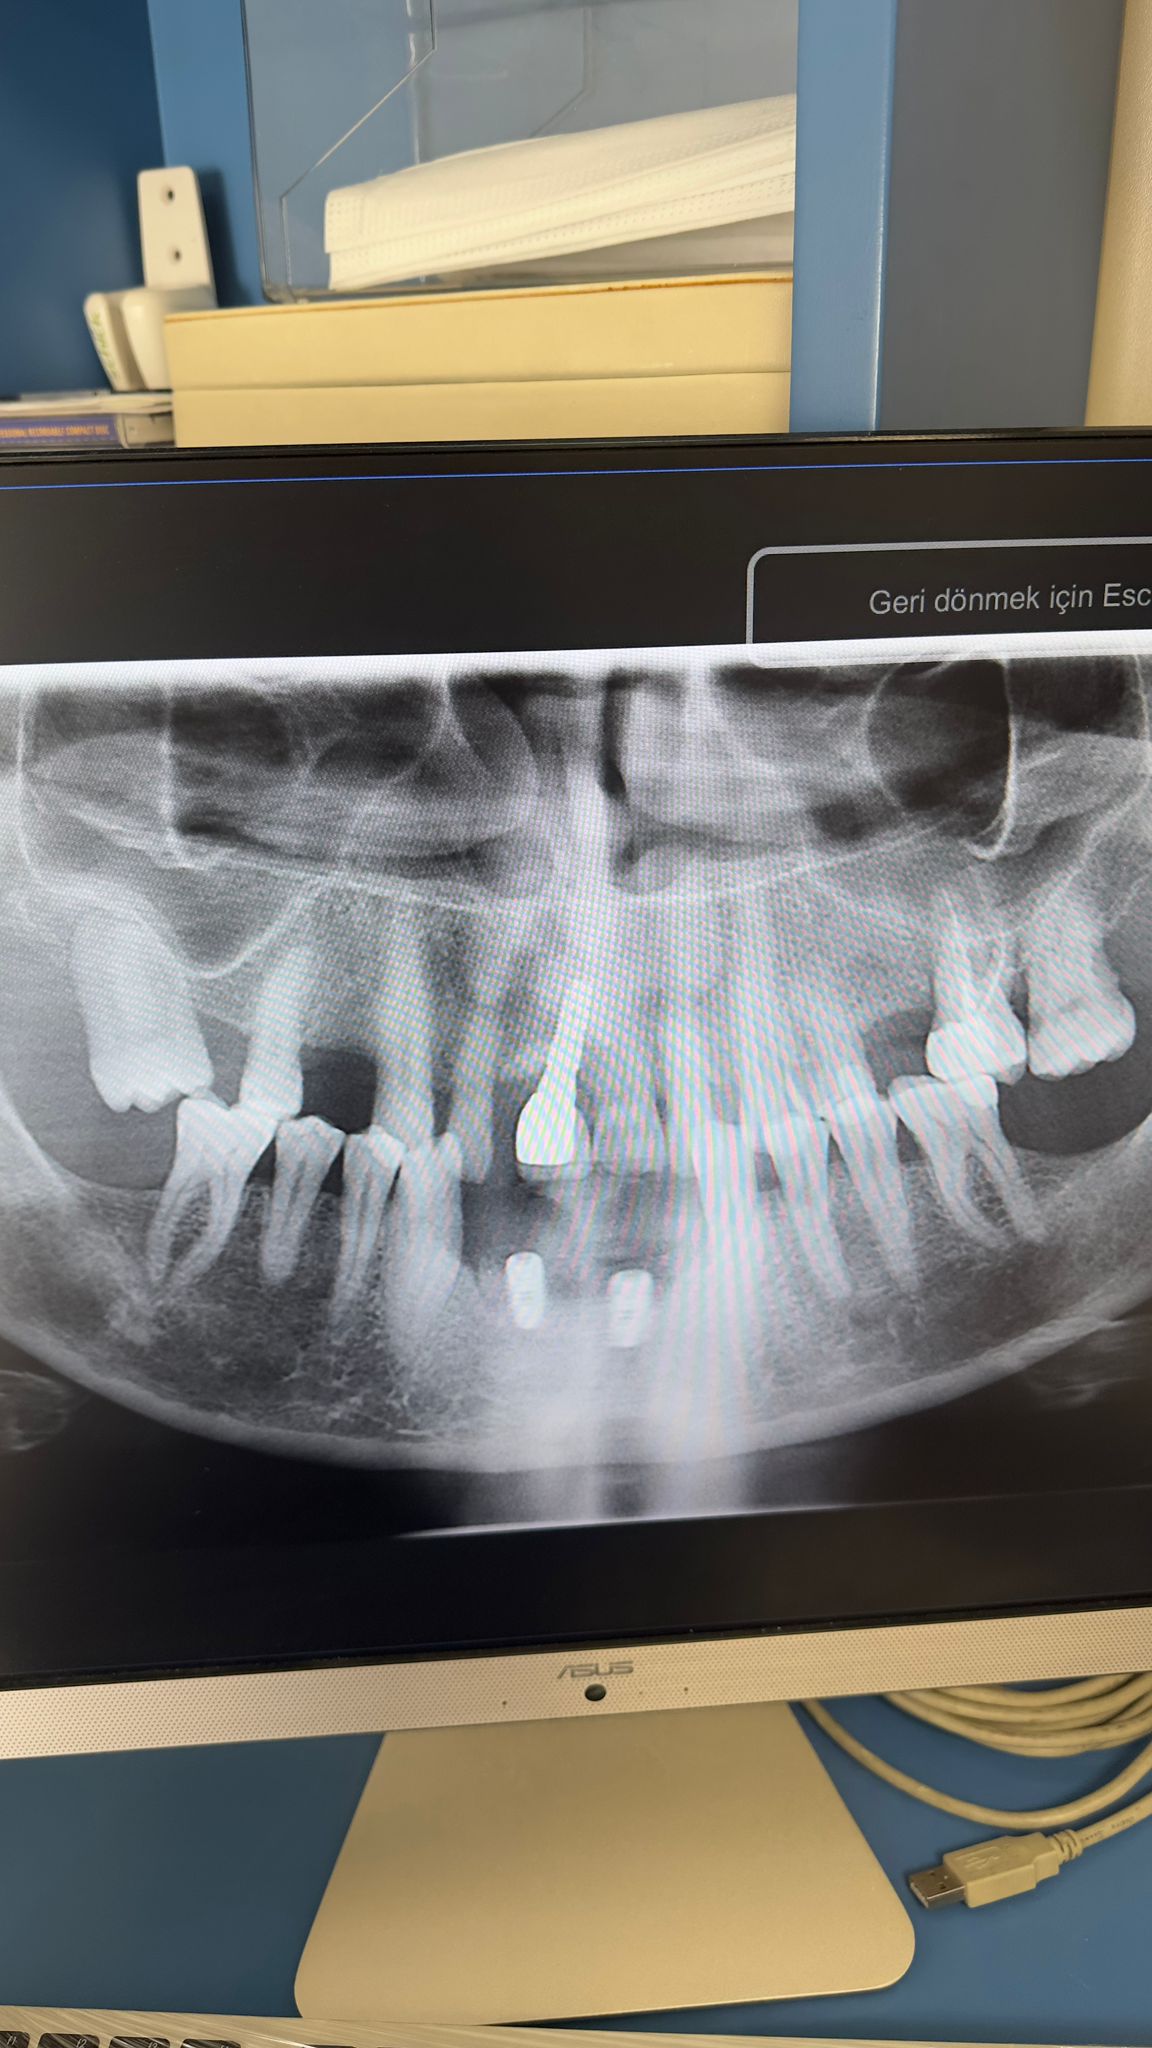

Ali Akıllıoğlu ( 01.09.1968) muayene edilip, panoramik film çekilmiştir. Alt ön bölgedeki 4 kesici dişinin sallandığı tespit edilmiştir. Kalp hastası olduğu için doktorundan lokal anestezi altında cerrahi işlem yapılabilmesi için görüş alınmıştır. Alt dört keser dişi çekilip , yan keserler bölgesine iki adt 3,2 mm çapında implant yerleştirilmiştir. Şimdi implantların osseintegrasyonu için beklenmektedir.3 Ekim 2025te muayene edildi. 07 Ocak 2026 da implantlar yerleştirildi.